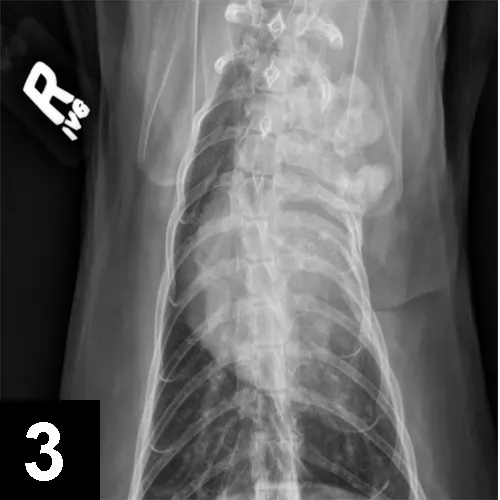

FIGURE 3

VD thoracic radiograph of a cat with left-sided Horner syndrome showing a sarcoma affecting the first 4 ribs and cranial thorax on the left, impacting preganglionic neurons.